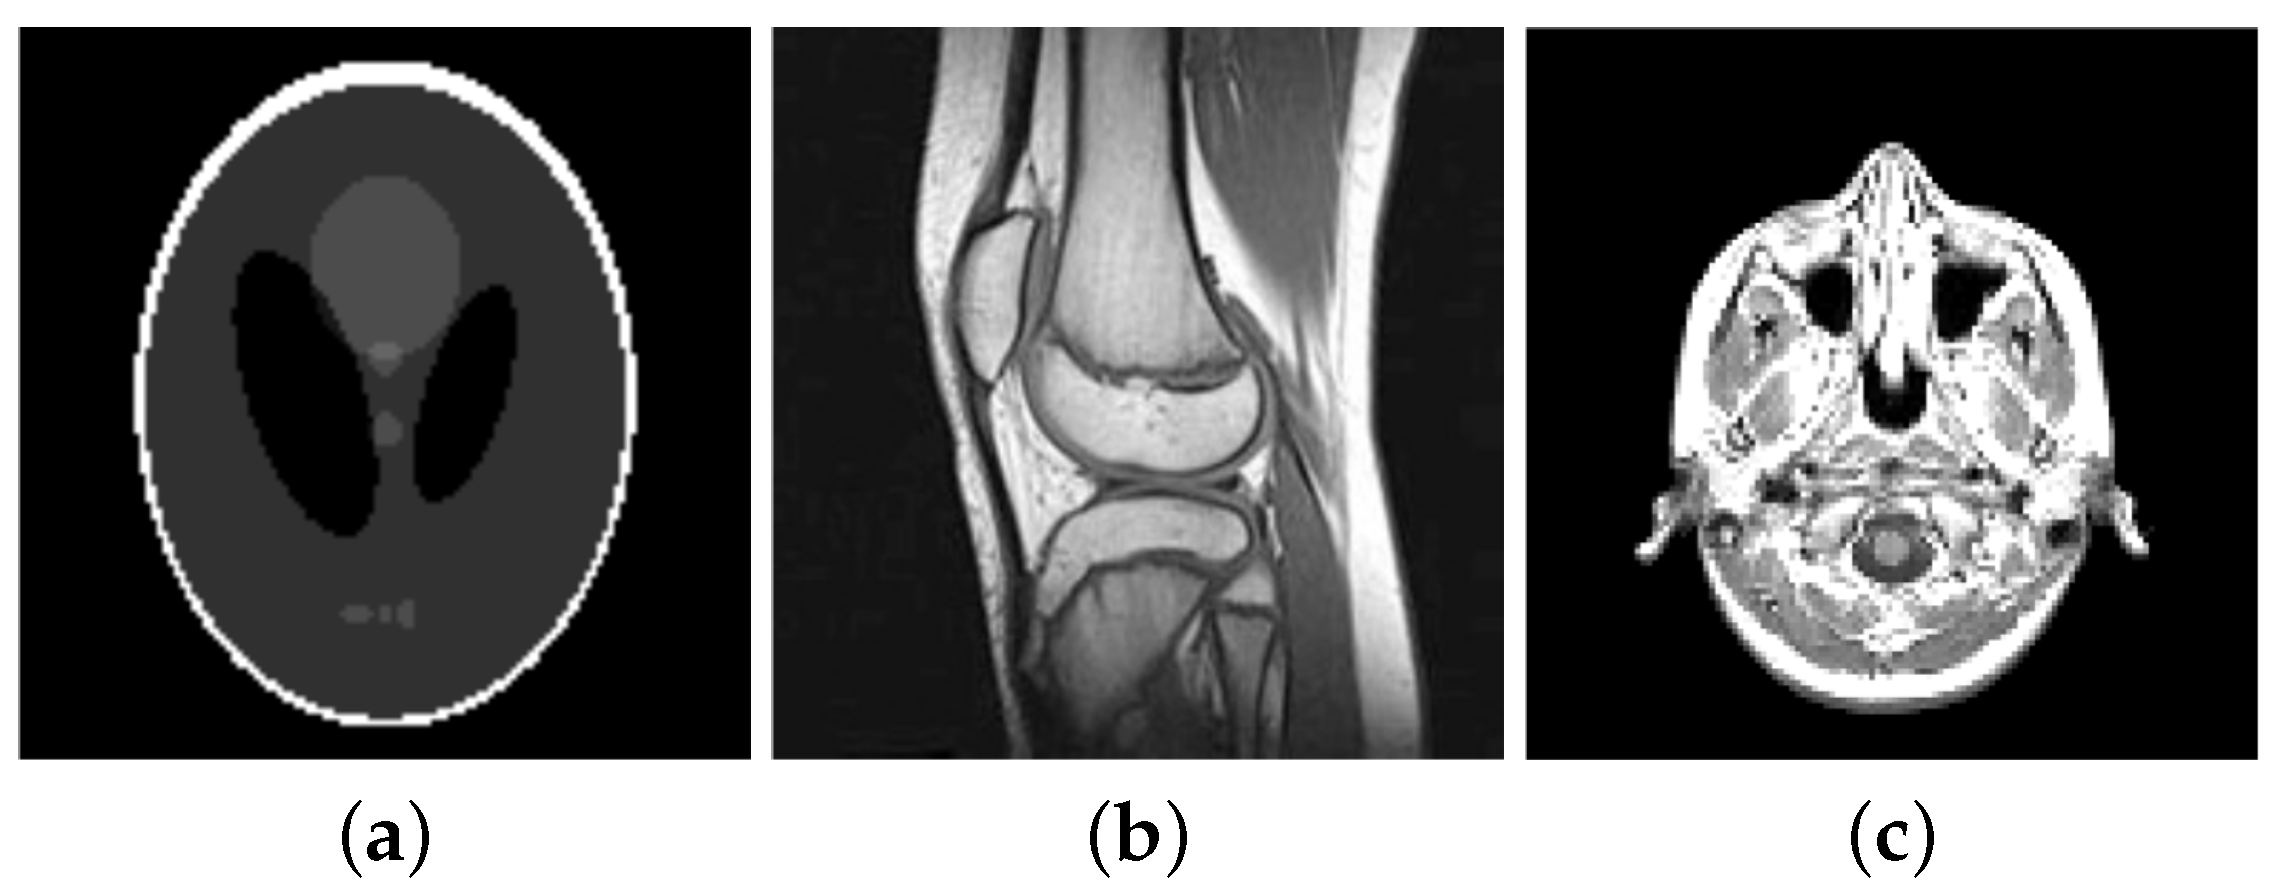

For our numerical studies we consider the images shown in Figure 1 of size 256 × 256 pixels and in Figure 2. The image intensity range of all original images considered in this paper is , i.e., and . Our proposed algorithms automatically transform this images into the dynamic range , here with . That is, let be the original image before any corruption, then . Moreover, the solution generated by the semi-smooth Newton method is afterwards back-transformed, i.e., the generated solution is transformed to . Note that is not necessarily in , except .

Figure 1.

Original images of size . (a) Phantom; (b) Cameraman; (c) Barbara; (d) House; (e) Lena; (f) Bones; (g) Cookies; (h) Numbers.

Figure 2.

Original images (a) Shepp-Logan phantom of size pixels (b) knee of size pixels (c) slice of a human brain of size pixels.